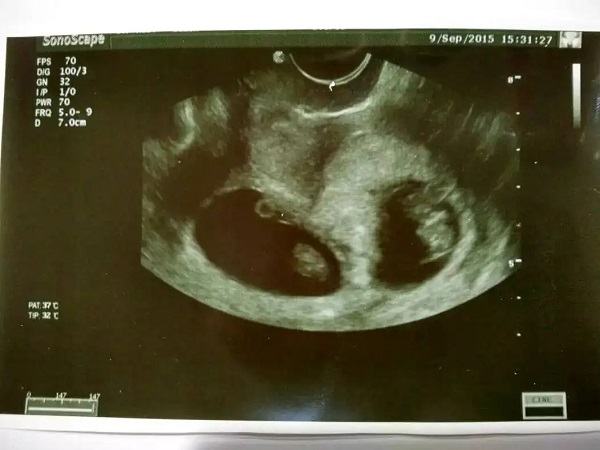

总而言之,通过血hcg数值的高低其实也是可以判断是单胎妊娠还是双胎妊娠的。当然一般还是建议大家通过B超检查进行判断,结果会更加准确,如果有两个孕囊或者是出现了两个胎心那么就一定是双胎。